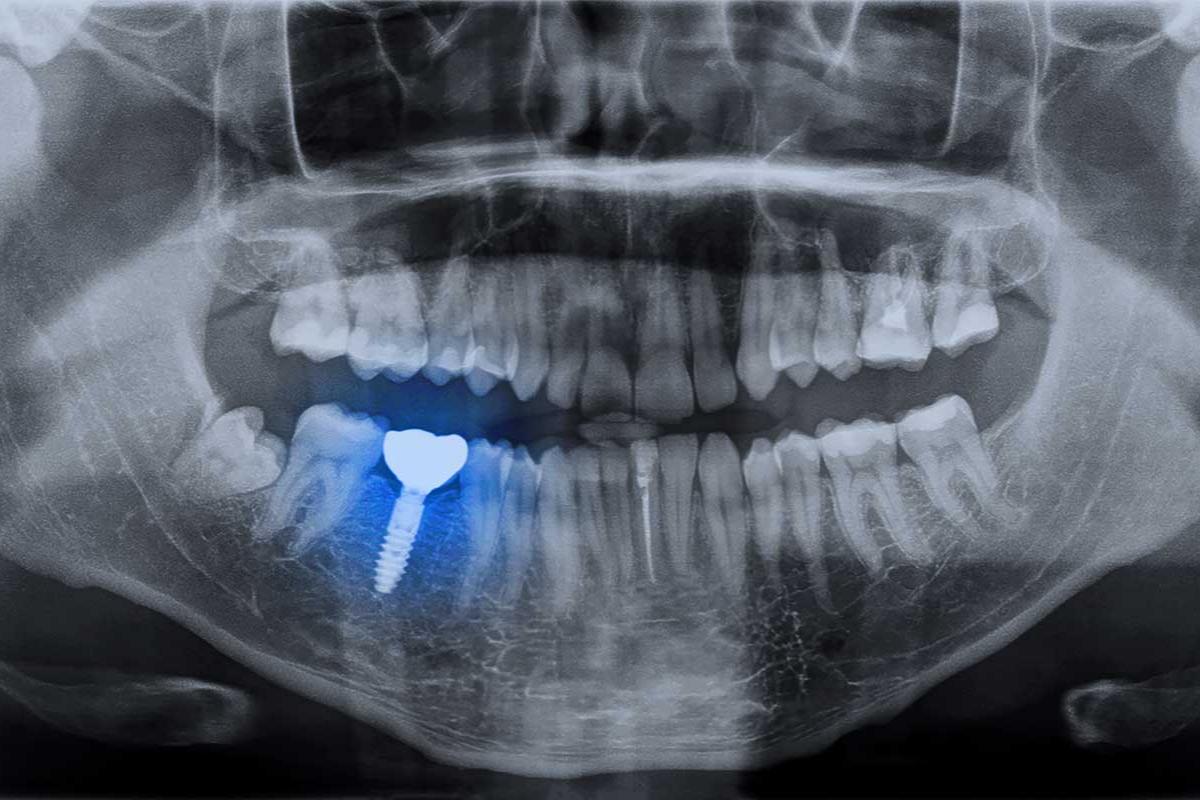

A dental implant is a small device that is placed surgically into the jawbone. There, the bone grows around the metal components. Over a period of weeks, this becomes a strong foundation for a fixture to be added to the top. First, the dentist will place an abutment, which creates a way to snap the crown into place. The dental crown appears like a natural tooth. They are typically highly durable, and your dentist can match the color, shape, and size of the surrounding teeth.

Once this process is in place, the dental implant functions like a traditional tooth root, supporting the crown for chewing and biting. Because of the location of the implant, they have a solid foundation, enabling a person to have nearly the same ability as they have with traditional teeth.

During the first step of the process, a person receives exams and x-rays to determine the mouth’s overall health. Your dentist will work closely with you to fully understand what to expect throughout the process. For many people, implants can be life-changing.